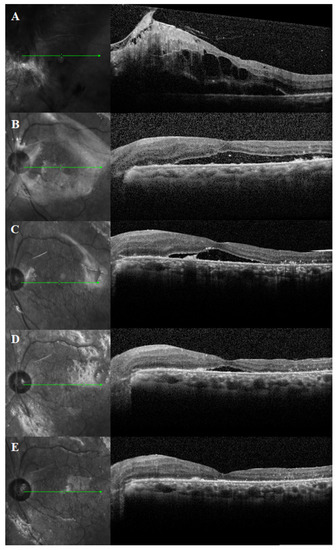

3.2. Duration of PSF and SRFH

| Duration of PSF, months | 4.4 ± 4.7 |